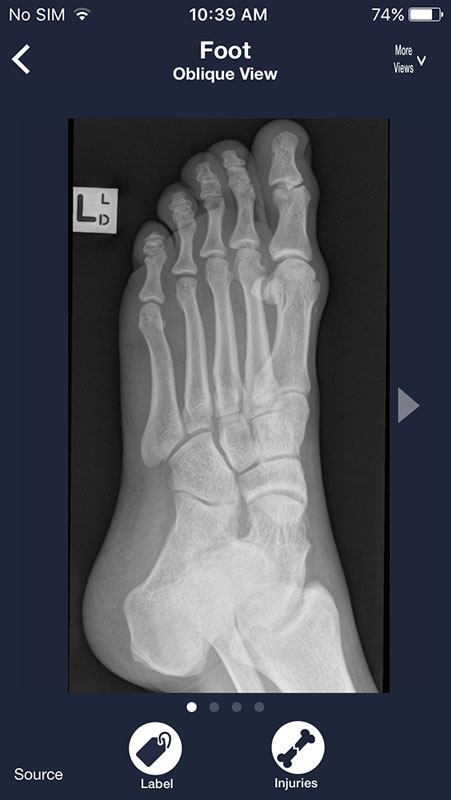

Most radiographs can be viewed from multiple angles. Simply tap on More Views above each image and choose between different views.

For example, you can view shoulder from AP view, apical oblique, or lateral Y, or choose to view chest X-rays from frontal or lateral view, which may be particularly useful to spot some abnormalities that might not be visible from frontal view (for example atelectasis).